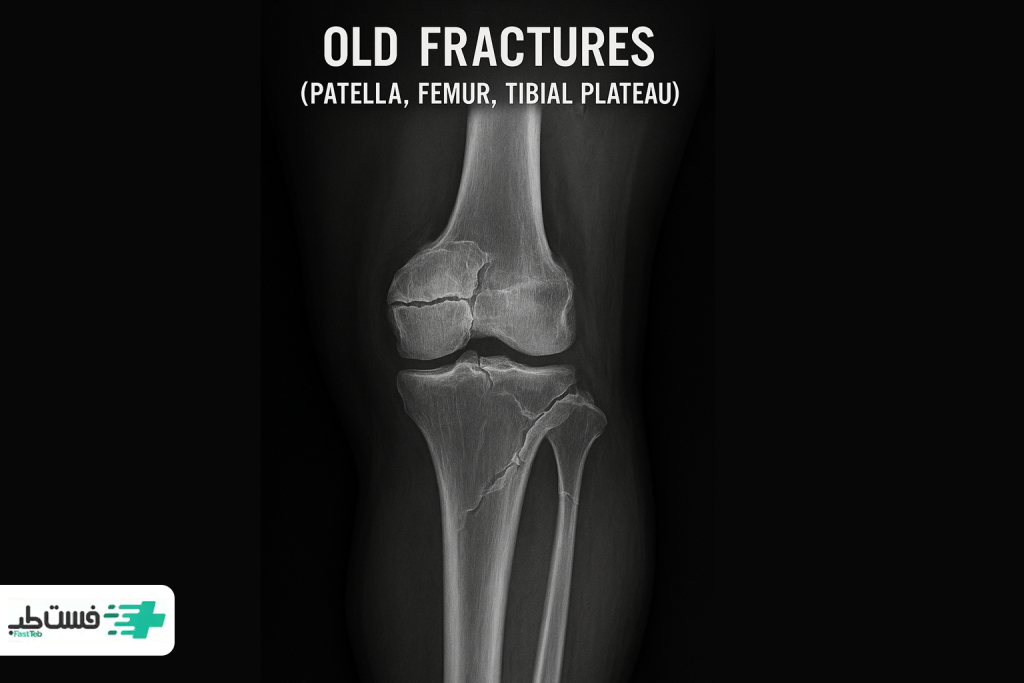

۱. جوشخوردن ناقص یا ناهماهنگ استخوان

وقتی استخوان در موقعیتی نادرست جوش میخورد، زاویه حرکت مفصل طبیعی زانو دچار اختلال میشود. این تغییر ممکن است جزئی باشد اما تأثیر آن در بلندمدت میتواند شدید باشد. بهویژه در شکستگیهای پلاتوی تیبیا یا کشکک، حتی چند میلیمتر اختلاف در راستا، میتواند منجر به درد مزمن، آرتروز زودرس و بیثباتی شود.

شکستگی کشکک (Patella Fracture)

کشکک زانو بیشتر در معرض ضربههای مستقیم قرار دارد. وقتی آسیب میبینه، باید حرکاتش محدود بشه اما نه بهطور کامل.

زانوبند مناسب باید از آن محافظت کرده و مانع خمشدن ناگهانی یا فشار نقطهای شود.

شکستگی پلاتوی تیبیا (Tibial Plateau Fracture)

در این مدل شکستگی، پایداری جانبی مفصل مهم است. مهم است که فشار وزن بدن، مستقیماً روی ناحیهی آسیبدیده وارد نشود.

در چنین شرایطی زانوبندهایی که پدهای جانبی دارند و فشار آنها قابل تنظیم است، گزینه بهتری هستند.